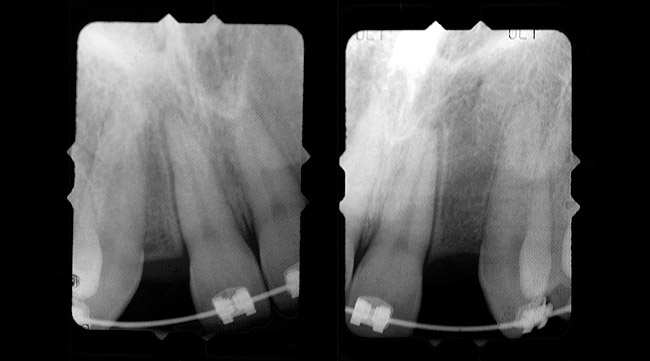

Periapical radiographs were taken to help determine the mesial-distal inclinations of the adjacent tooth roots (Figure 1). The radiographs revealed a serious issue, convergent roots for the right canine and right central, which eliminated that area as a potential implant-receptor site. The space between the left central and canine teeth was minimal, although the roots were relatively parallel. Clinical examination (manual palpation of the root eminences superiorly to the vestibule on the right side) confirmed the root convergence (Figure 2). The flat, wide zone of the keratinized tissue and lack of interdental papilla was evident for the missing right lateral incisor. There was a marked difference in clinical appearance for the left lateral, which could impact the eventual plan of treatment (Figure 3). Other significant clinical findings included bilateral facial bone concavities, which existed as a result of the congenitally missing tooth roots. As a diagnostic cue to the underlying bone topography, it is important to follow the demarcation between attached and unattached gingival tissue, and note the crestal width of the available keratinized tissue (Figure 4).

Figure 1  PRE-TREATMENT DIAGNOSTICS Pretreatment radiographs revealed convergent roots for the right canine and right central.

Figure 1